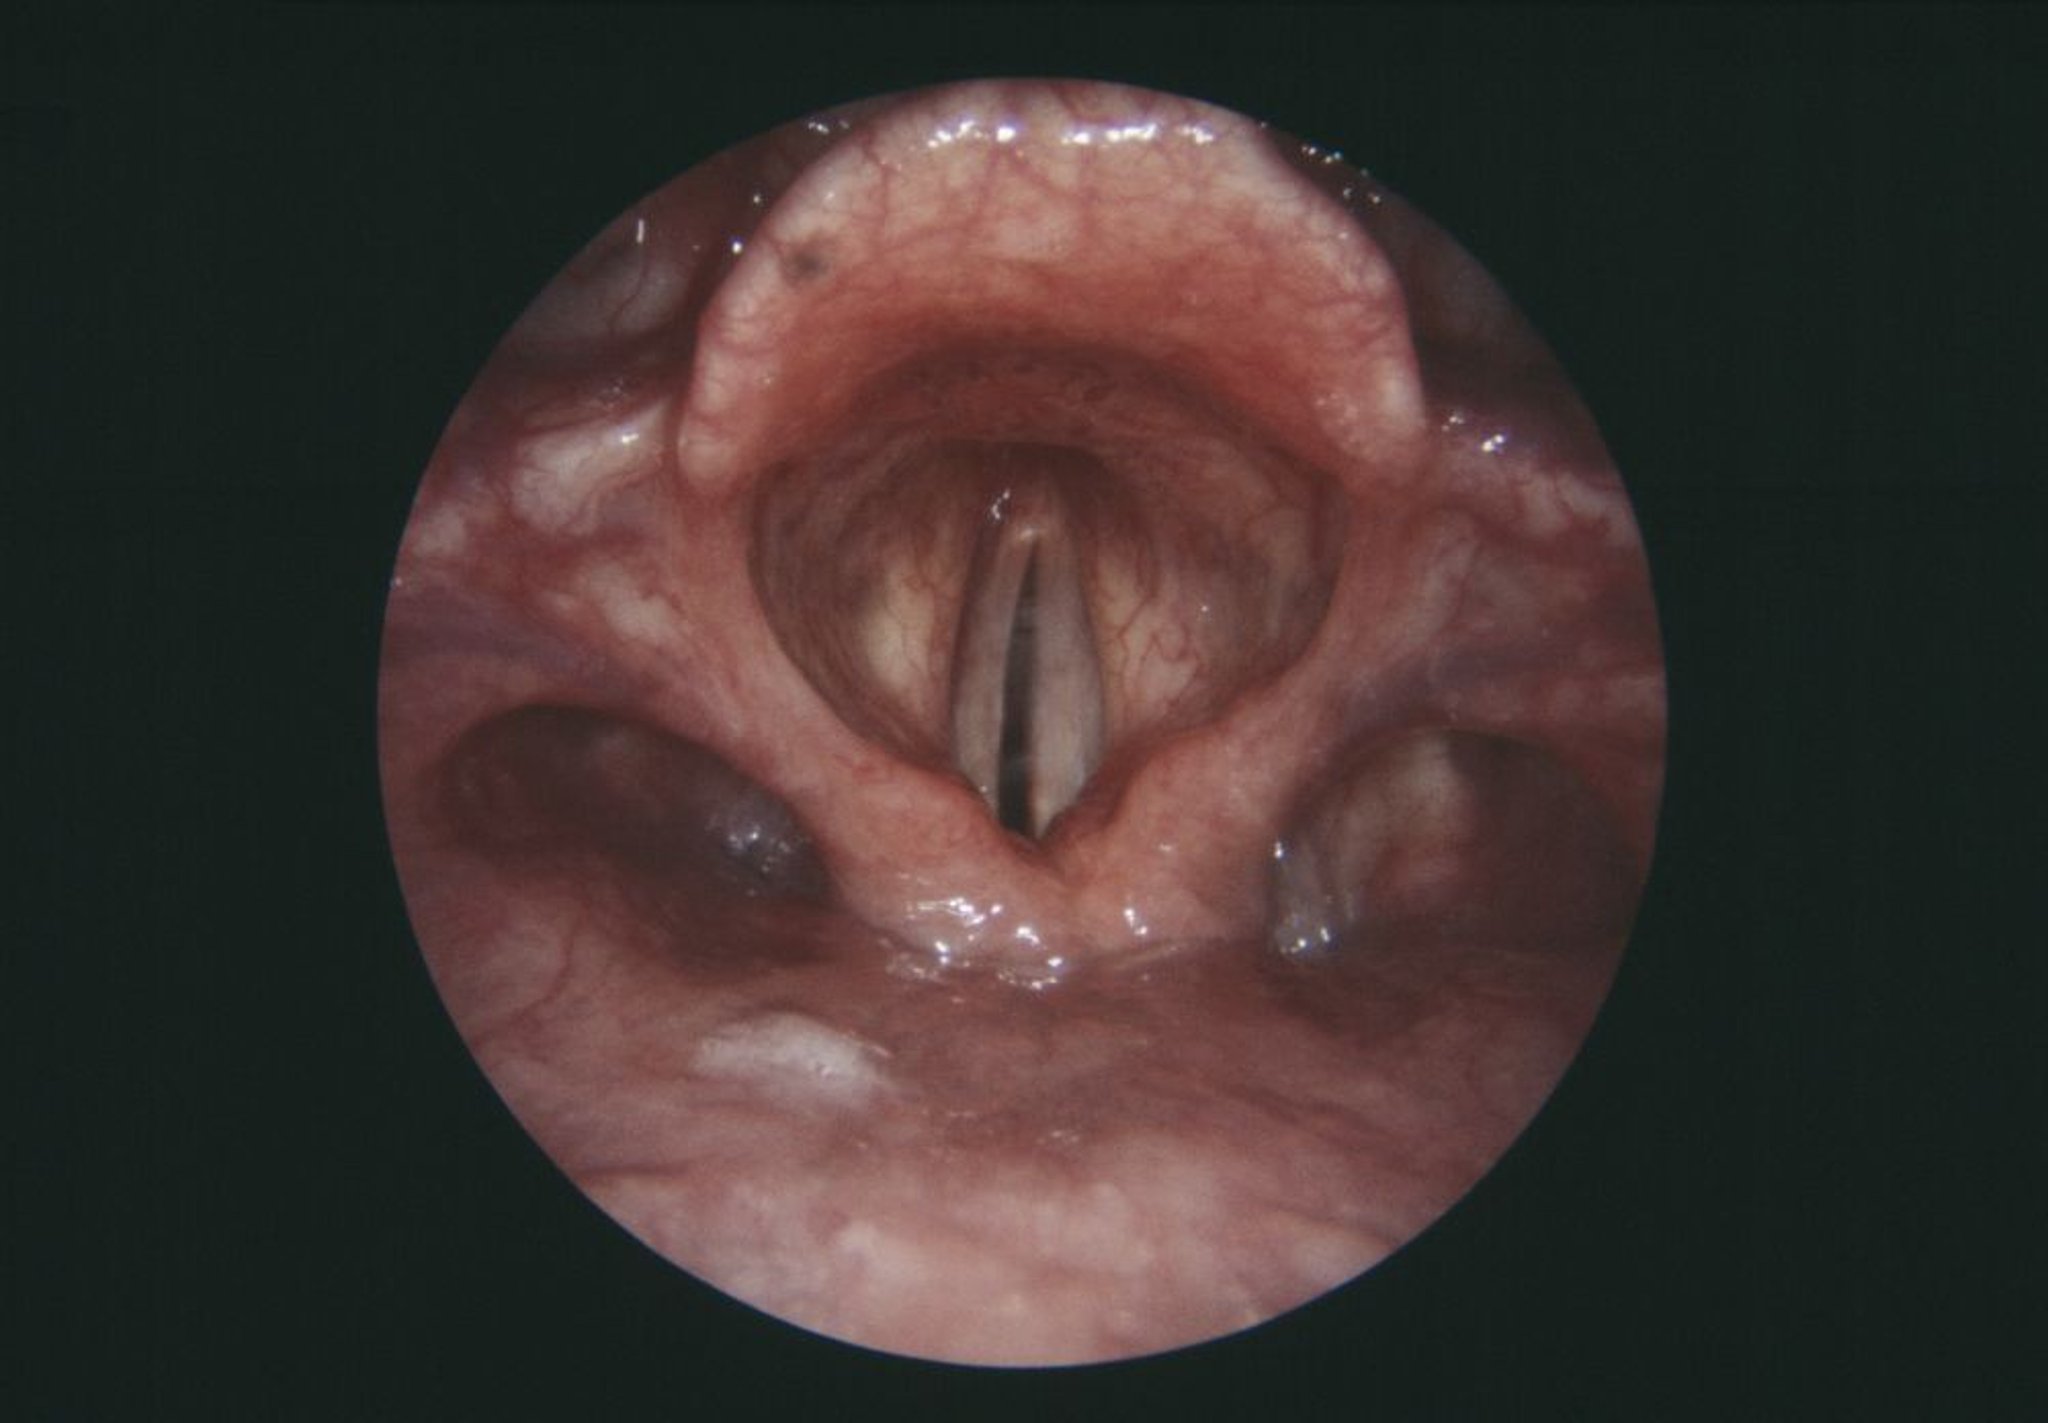

Это эндоскопическое изображение гортани (голосового аппарата) показывает парализованную правую голосовую связку (серая, в центре слева).